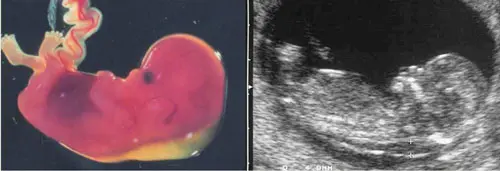

Ultrassom mostrando translucência nucal aumentada acima do percentil 95 — indicação de investigação complementar

Exemplo de translucência nucal aumentada.